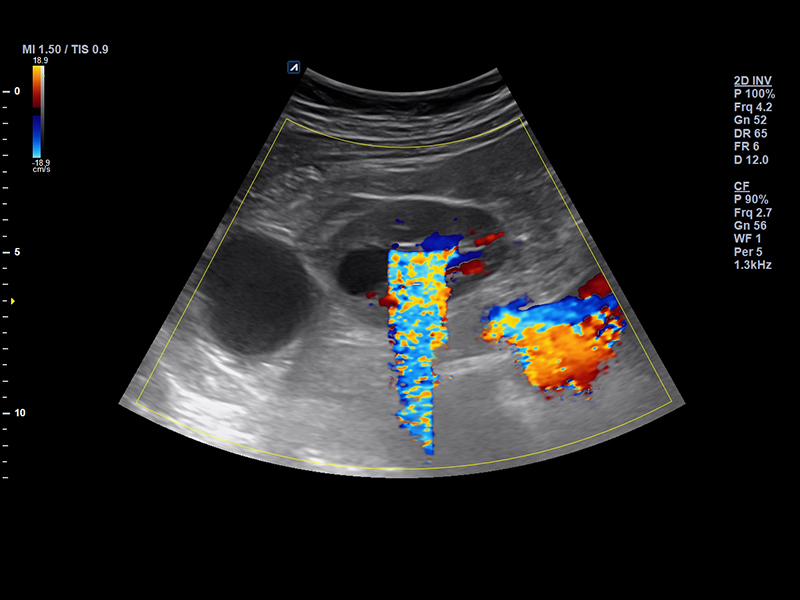

SC1-7H

X+ Crystal Signature™ convex transducer(1~7MHz)

Application:

Abdomen, EM, Gynecology, Obstetrics, Pediatric, Urology